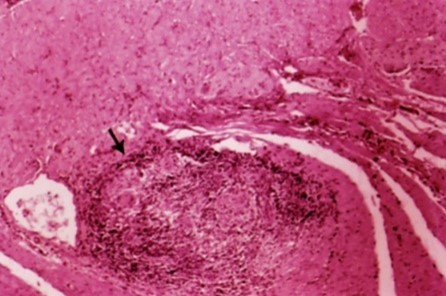

Vilken sjukdom och vad ses?

Crohns sjukdom med ett granulom

När kan detta ses vid mikroskopisk bild?

Crohns